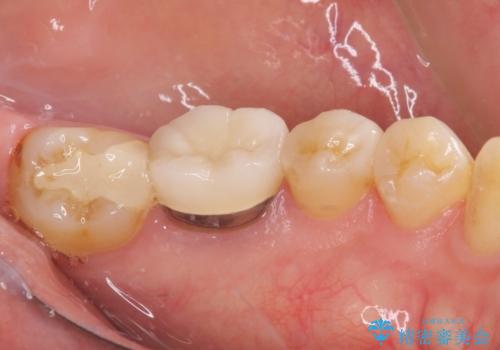

- 冷たいものがしみるとのことで来院された患者様です。

診査を行った結果、第一小臼歯にある樹脂の詰め物(コンポジットレジン)と歯の境目が痛みの原因であることが分かりました。

また、隣接する第二小臼歯も虫歯になっていることも分かったため、2歯を同時に治療するにしました。

下顎の目立つ位置であるため、セラミックインレーによる修復治療を行うこととしました。

精密に型取りを行ったセラミックインレーを装着したことで、治療後にはしみたり痛んだりという症状は治まりました。